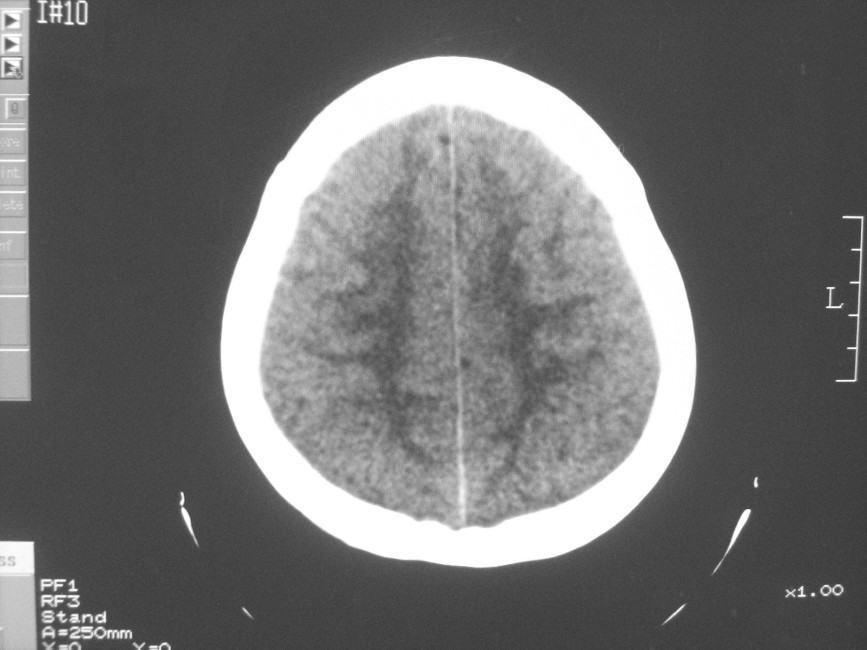

以下是引用zzyy在2008-6-16 10:13:00的发言:[br]两侧脑白质呈对称性密度减低,病儿有发热及脑膜刺激征。考虑急性病毒性脑炎。